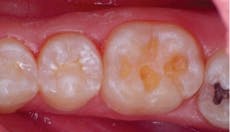

Occlusal prep

Fortunately, dental manufacturers have risen to the challenge and worked diligently to improve the tools at dentists’ disposal. For example, significant improvements in our ability to diagnose caries have emerged in various forms, from laser fluorescence (DIAGNOdent, KaVo), and LED fluorescence (Midwest Caries I.D., DENTSPLY/Professional; Spectra Caries Detector, Air Techniques; SOPROLIFE Caries Detector, Acteon), to alternating electrical current impedance (CarieScan PRO, CarieScan Global), and digital radiography with caries-specific software (LOGICON, Carestream Dental).

Occlusal composite fill

Additionally, restoring these detected lesions can take on many forms to keep with the minimally invasive theme, including no preparation options such as ICON (DMG/America), to glass ionomers and direct composite resins. Many times, composites offer dentists the most simple and cost-effective way to create esthetic restorations, but not without a significant learning curve. It’s been more than 50 years since Buonocore thought of bonding to enamel with the introduction of acid-etching, and though the resin-based fillings of that period were quite inferior to those available today, issues related to material properties and handling characteristics, as well as the clinician’s skill, are still key to the success or failure of a composite restoration.